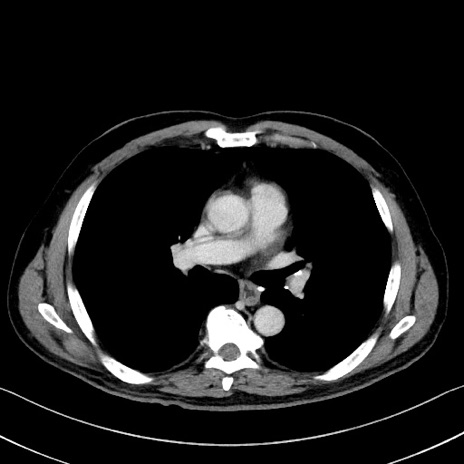

症例35(横断像)

【症例】70歳代 男性

【主訴】腹部膨満、嘔吐

【現病歴】昨日より腹部膨満感出現。本日増悪し、仙痛出現。嘔吐あり、受診。

【既往歴】糖尿病、胆摘後

【身体所見】BP 149/80mmHg、HR 74/min、BT 35.9℃、腹部:膨満、軟、圧痛なし。腸雑音減弱あり。上腹部正中切開瘢痕あり。

【データ】WBC 13500、CRP 1.72